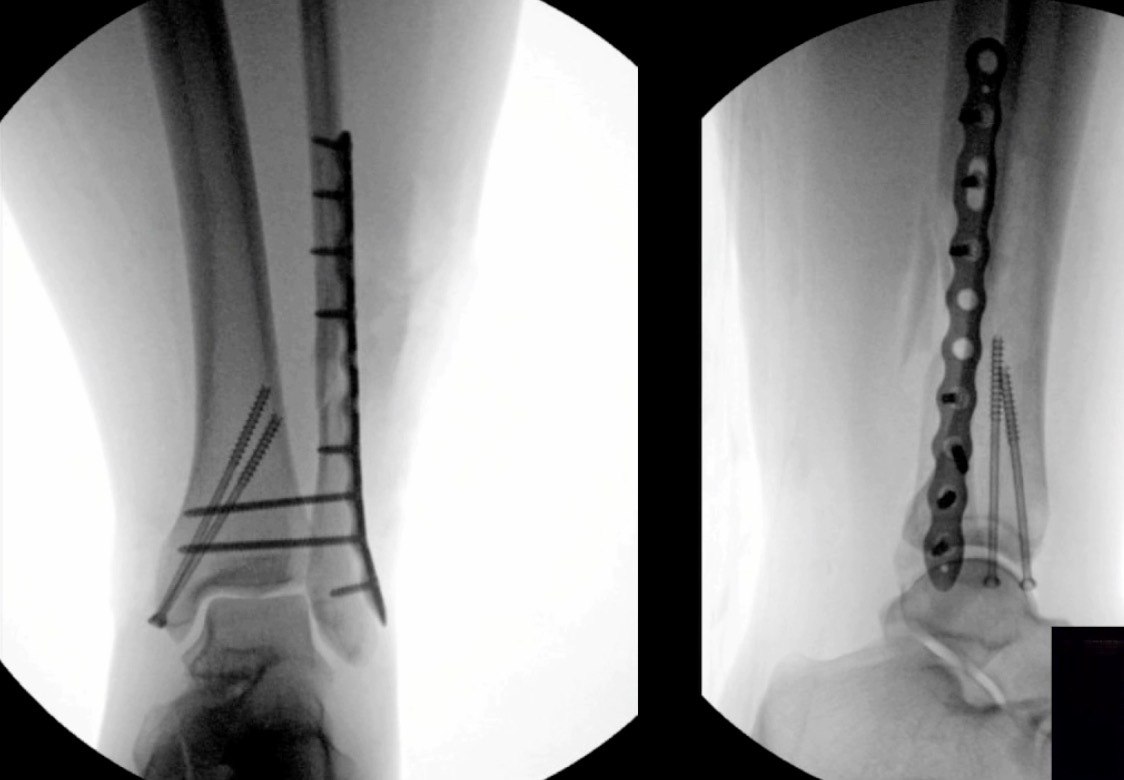

Our Randomized Controlled Trial specifically excluded those, because when I was a resident, syndesmosis injury was kept non-weight-bearing for three months, that was the standard (three months in a cast). Unfortunately, the treatment is sometimes worse than the disease. There is much controversy in terms of weight bearing for syndesmosis injuries, and not as much evidence on this specific injury compared to previously discussed ankle fractures. Figure 7 is a type of fracture we’re referring to: After you fix it, what do you do next?

A small RCT (Khaleel M, et al. Foot Ankle Orthop. 2024;9(4)) was conducted assessing syndesmosis injuries comparing early versus delayed weight-bearing. They had a relatively small sample size: only 16 patients in one group, 23 in the other group, but they did show that there was potential improvement in range of motion with the early group, and there was no catastrophic failure. This raises an interesting question: “can we allow early weightbearing after syndesmosis fixation?”, and we need more studies on this specific topic.